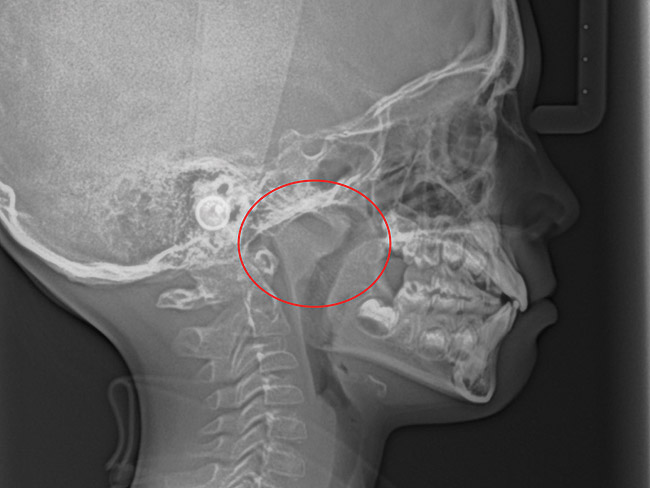

(21.) Six-year-old male presents nocturnal bruxism, habitual snoring, and behavioral issues. PSG reports an AHI of 9.6/hr and respiratory effort–related arousal (RERA) of 14.2/hr (Case provided by Kathy French, DDS).

Figure 21

(22.) Radiograph highlights the obstructed nasal airway preoperatively. Three months after T&A, another PSG demonstrated an AHI of 0.3 and RERA of 0.0/hr.

Figure 22